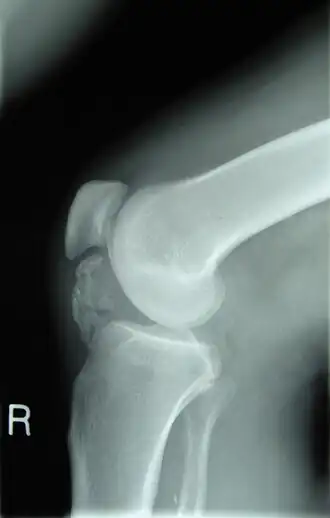

No caso do trauma ósseo, as fraturas são uma das principais formas de patologia, ocorrendo quando o osso é submetido a forças anormais de tensão, compressão ou torção. As fraturas podem ser classificadas como completas, incompletas (fratura em galho verde), cominutivas ou compostas. Algumas fraturas, como as resultantes de traumas patológicos, ocorrem devido ao enfraquecimento prévio do osso por doenças como a osteoporose.

Já a artrite, a inflamação das articulações, pode ser causada por trauma ou infecção. A osteoartrite é uma das formas mais comuns, resultando na destruição da cartilagem articular e na formação de osteófitos ao redor das articulações, muitas vezes associada ao envelhecimento.